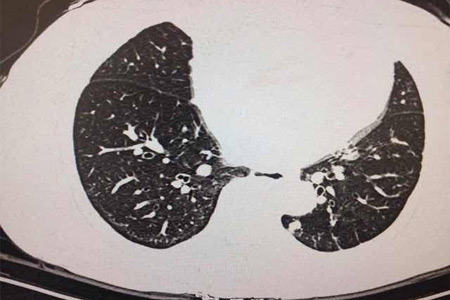

胸部X光和CT掃描:胸部X光和CT掃描是常用的檢查方法,可以發現肺部腫塊、結節等異常病變。然而,這些方法往往難以區分良性和惡性病變,需要進一步檢查。